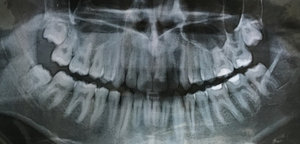

Добрый день . Для начала рекомендую сделать панорамный снимок и обратиться к хирургу-стоматологу. На месте по снимку можно диагностировать вашу проблему.